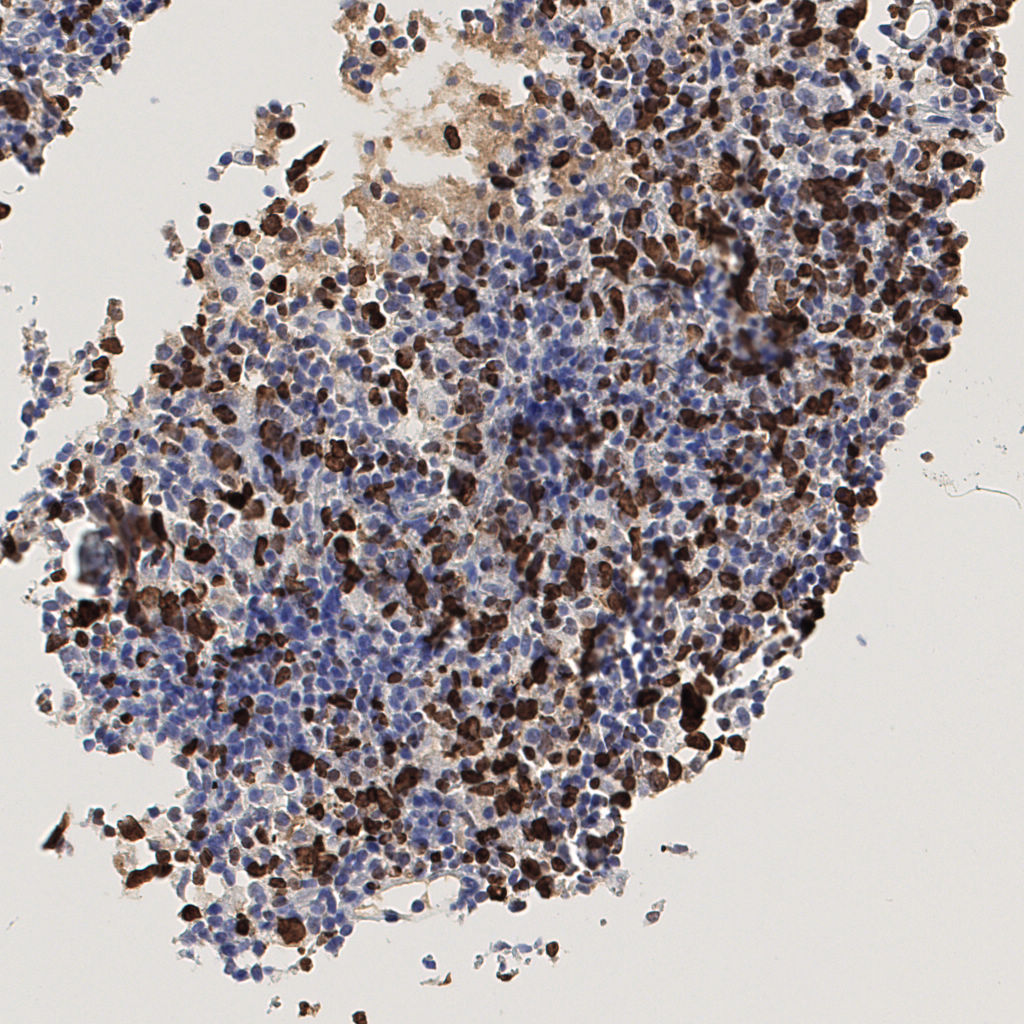

7.85%

Ki67 指数

阴 1104

阳 94

切片统计

总切片

1953

有效

288

已标记

有效率

15%

标记后

标记前